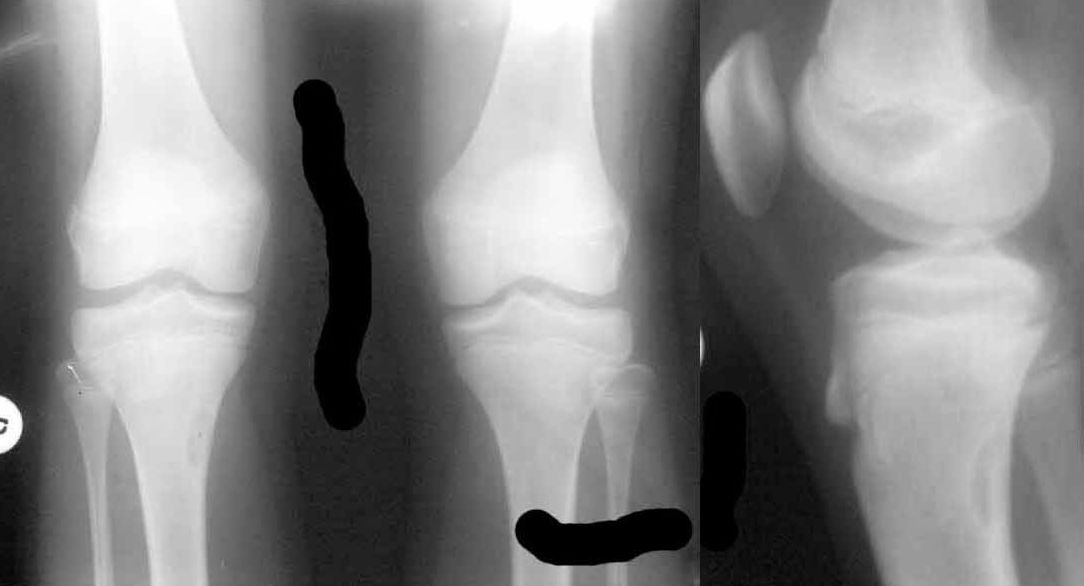

Коллеги, обратились педиатры с вопросом:"Девочке сейчас 12.5 лет. Летом этого года стартовал пубертат, начала вытягиваться.

В течение лета были активные физические нагрузки, в августе - длительные пешие походы в горах. С сентября стали появляться боли в коленных суставах, связанные с подъемом по лестнице и при приседании. Боли непостоянные, то в одной, то в другой ноге, иногда одновременно в обоих коленях. В покое и при обычной ходьбе боли не отмечаются. 18.01.2011 сделали снимки коленных суставов - выявлен очаг фиброза в правой большеберцовой кости?"

Вариант фиброзной дисплазии (фиброзный кортикальный дефект). В плане обследования КТ. В плане лечения - наблюдение, Ro-гр. раз в полгода. Если не увеличивается в размерах оставить в покое.

Согласен с Алексеем. Фиброзный метафизарный кортикальный дефект - особенность формирования костей в местах крепления сухожилий наиболее активных мышц, клинически не проявляется, выявляется у 15% здоровых подростков, занимающихся спортом. самостоятельно замещается нормальной косчтной тканью после окончания полового созревания, оперативного лечения не требует. С уважением, врач-рентгенолог УНИИТО, Зельский И.А.

Osgood-Schlatter est', esho imeetsya kista bolshebertsovoy kosti po medial'noy poverkhnosti, vidna na obeikh proektsiakh.

на данных снимках не очень хорошего качества сканирования можно думать об очаге фиброзной дисплазии. Данное место наиболее частое для подобных образований, мне неоднократно доводилось оперировать эту патологию- экономная резекция с замещением дефекта Коллапаном. Можно сделать несколько снимков в косых проекциях и, если доступно, МРТ, КТ даст слишком большую дозу ребенку.

1. У Вашей пациентке метафизарный фиброзный дефект проксимального отдела большеберцовой кости. Локализуются данные образования в местах прикрепления активных групп мышц, связаны могут быть с повышенными физическими нарузками (как в Вашем случае). При данной клинике и рентгенологической картине необходим разгрузочный режим (исключить бег, прыжки) и наблюдение. В настоящий момент угрозы патологического перелома нет, поэтому более оправдана консервативная тактика.

2. О болезни Осгуда-Шлаттера (были предположения в комментариях) нельзя судить только по рентгенологической картине, тем более что она соответствует норме - нет изменений структуры, отсутствует фрагментация. Остеохондропатии в данном случае без клиники быть не может.

Это вариант фиброзной остеодисплазии- экстакортикальная неоосифицирующая фиброма проксимального отдела б/берцовой кости. Течение , как правило благоприятное , наблюдайте и всё будет ОК!

Фиброзная дисплазия (кортикальный дефект). Скорее всего случайная находка. Тактика:если дефект более 1/3 диаметра б\б кости - оперировать (риск возникновения перелома), если менее - нет. В данном случае - наблюдать (а можно и не наблюдать, оставить в покое). Боли связаны с чем-то другим (скорее всего перегрузки - на месяц-другой освободить от тренировок).